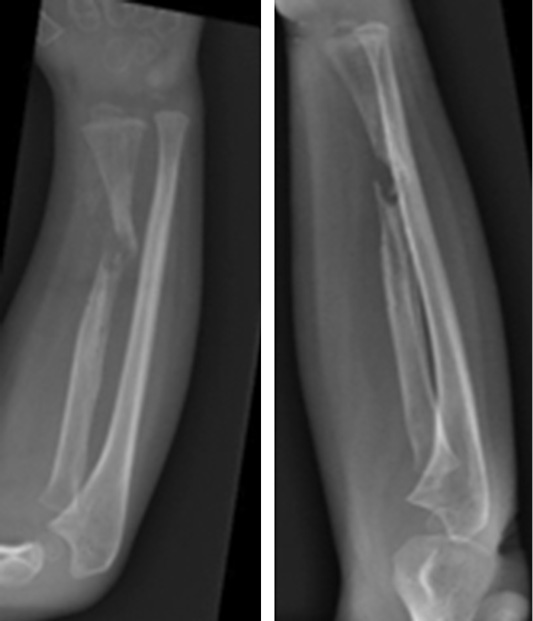

В июне 2015 г. были отмечены признаки местной резорбции кости в области переломов, и в связи с подозрением на синдром Горхема – Стоута проведены магнитно-резонансная томография и консультация со специалистом по редким заболеваниям (рис. 3).

Рис. 3. В области переломов — признаки локальной резорбции кости

Была выполнена биопсия кости, и по заключению двух разных итальянских центров синдром Горхема – Стоута был исключен, так как выявлены реактивная костная ткань с аномальной васкуляризацией, некротические костно-хрящевые фрагменты и гигантские мононуклеарные клетки. Несмотря на то что пациент поступил в нашу больницу с этими результатами, было решено повторить биопсию, и исключение синдрома Горхема – Стоута было подтверждено. После этого провели дополнительные лабораторные исследования и консультации с большим количеством специалистов, чтобы исключить все причины, которые могли привести к обширному остеолизу. Спустя 11 мес. после последней травмы произведена новая операция на месте перелома с иссечением ткани и имплантированием аутологичного трансплантата малоберцовой кости с факторами роста костного мозга. Трансплантат стабилизирован спицами Киршнера (рис. 4).

Рис. 4. Рентгенограмма до и после иссечения ткани, аутологичная малоберцовая кость с костномозговыми факторами роста, аутотрансплантат стабилизирован интрамедуллярной спицей Киршнера